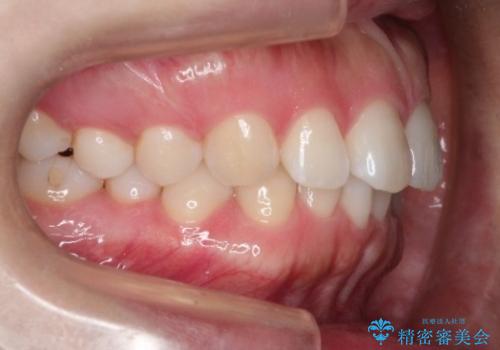

- 前歯の歯並びの改善を希望され来院された患者様です。

初診時の歯並びの状態としては、下顎前歯に及ぶの中等度のがたつき(叢生)があり、前歯が深く噛みこんでいる状態でした。

抜歯は行わず歯列弓の拡大やディスキング(歯と歯の間の隙間を作る処置)を行い叢生を改善しました。

見た目、嚙み合わせ及び、治療期間や施術内容に大変ご満足いただきました。